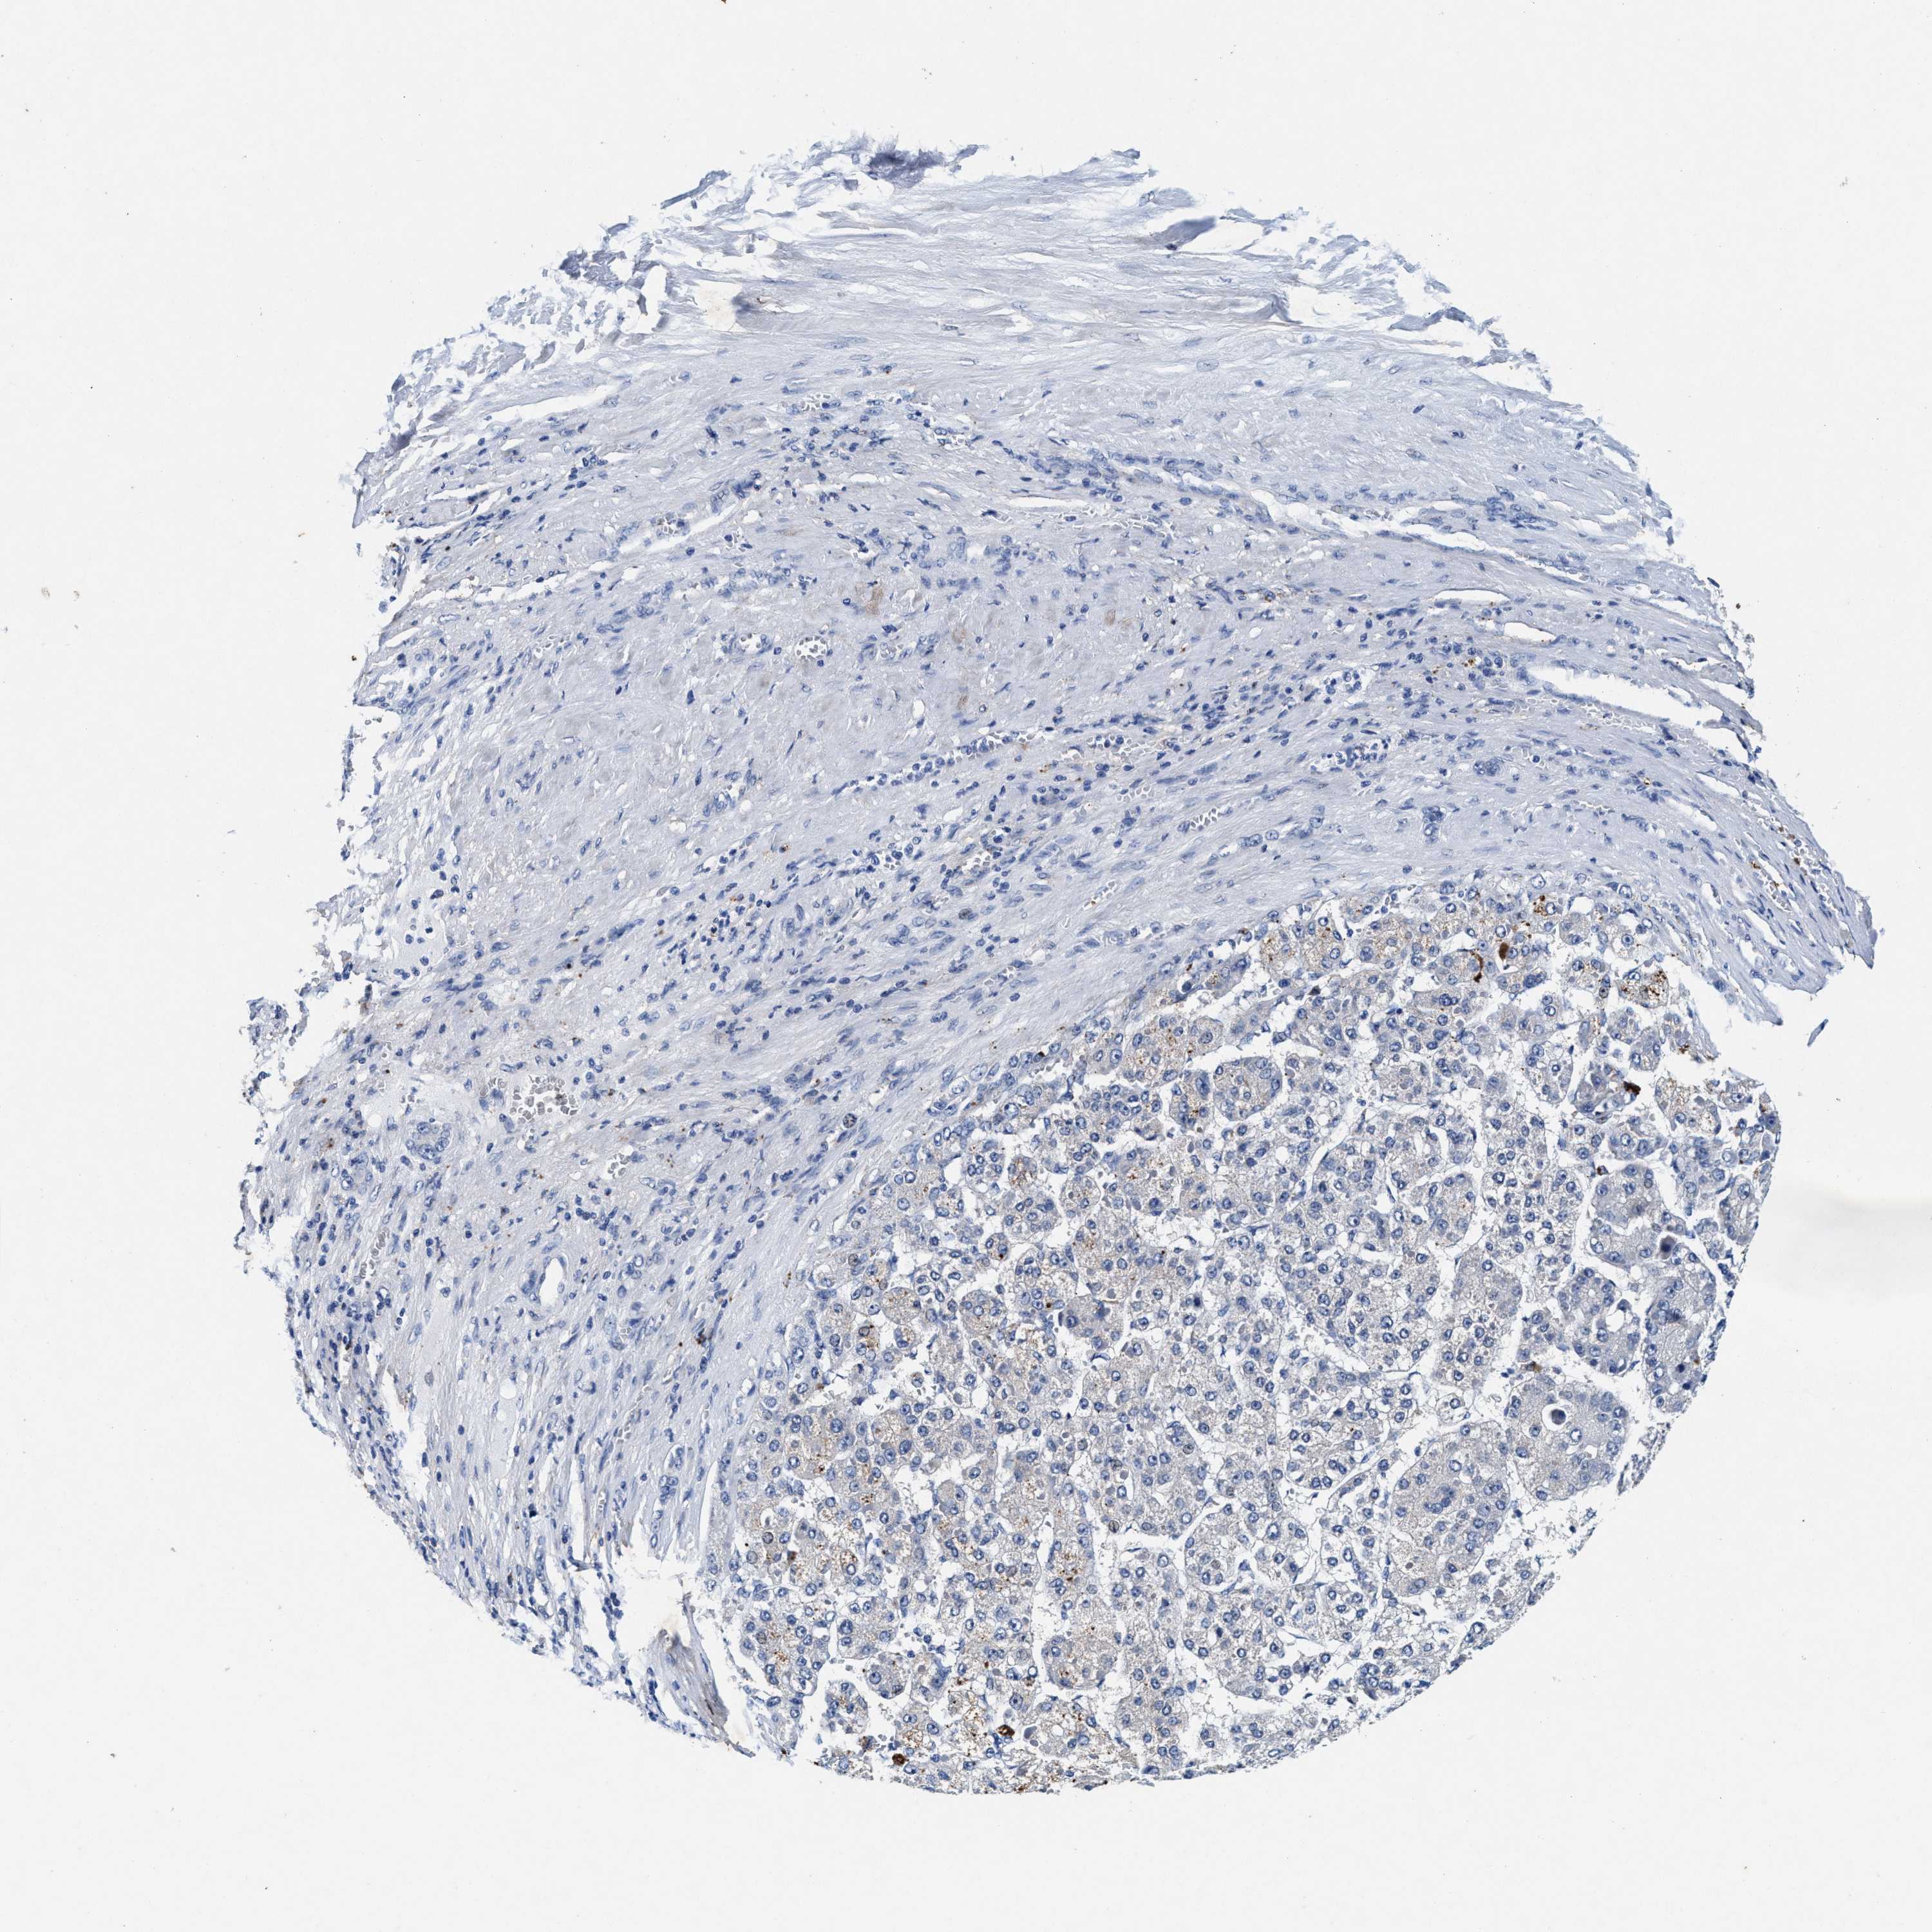

LIVER CANCER - Protein expressioni

A mouse-over function shows sample information and annotation data. Click on an image to view it in a full screen mode. Samples can be filtered based on level of antibody staining by selecting one or several of the following categories: high, medium, low and not detected. The assay and annotation is described here.

Note that samples used for immunohistochemistry by the Human Protein Atlas do not correspond to samples in the TCGA dataset.

Antibody stainingi

Antibody staining in the annotated cell types in the current human tissue is reported as not detected, low, medium, or high, based on conventional immunohistochemistry profiling in selected tissues. This score is based on the combination of the staining intensity and fraction of stained cells.

Each image is clickable and will lead to virtual microscopy that enables deeper exploration of all samples and also displays staining intensity scores, fraction scores and subcellular localization as well as patient and tissue information for each sample.

Antibody CAB022694

Staining

High

Medium

Low

Not detected

Intensity

Strong

Moderate

Weak

Negative

Quantity

>75%

75%-25%

<25%

None

Location

Nuclear

Cytoplasmic/membranous

Cytoplasmic/membranous,nuclear

Cholangiocarcinoma

Carcinoma, Hepatocellular, NOS